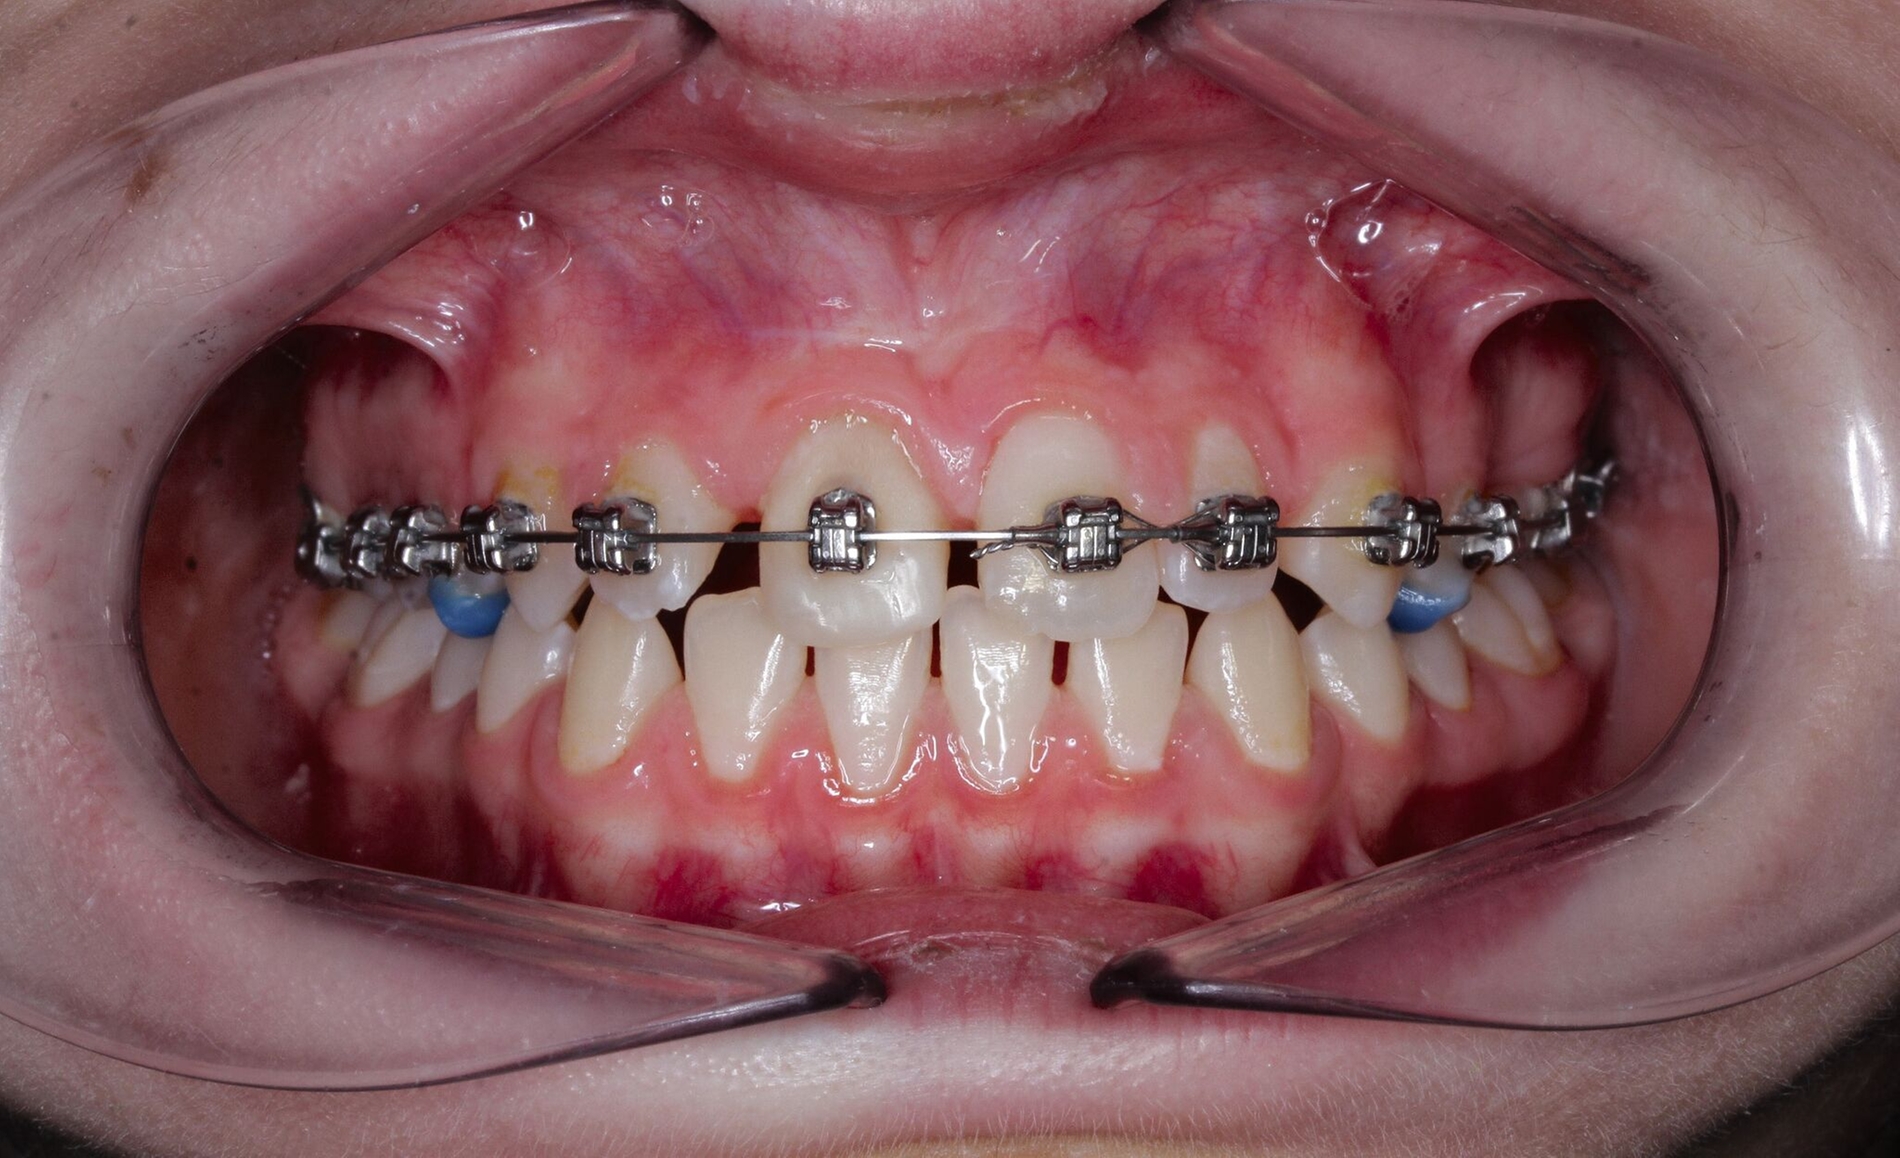

Ein neunjähriges Mädchen hatte bei einem Schlittenunfall den rechten oberen mittleren Schneidezahn verloren. Der Zahn 11 war nach einer extraoralen Lagerungszeit von mehr als 24 Stunden alio loco replantiert und mit einem Titan-Trauma-Splint von Zahn 12 bis 22 geschient worden. Drei Monate nach dem Unfall stellte sich die Patientin mit folgendem Befund vor (Abbildung 2):

Aufgrund der infausten Prognose des replantierten Zahnes 11 entschieden wir uns für die Milchzahn-Transplantation von 83 nach 11, da dieser die längste Wurzellänge aller vier Milcheckzähne besaß. Im selben Eingriff wurde der replantierte Zahn 11 entfernt und der Milcheckzahn 83 in die Lücke 11 transplantiert. Das Transplantat wurde für drei Wochen mit einer Überknüpfnaht fixiert, die mit Kunststoff (Tetric EvoFlow®, Cavifil, Bleach XL) adhäsiv gesichert wurde (Abbildung 3a). Nach der Entfernung der Naht zeigte sich ein reizlos eingeheiltes Transplantat mit Lockerung I. Grades, negativem Perkussionstest sowie reizlosen gingivalen Verhältnissen bei einer Taschentiefe von 1 mm (Abbildung 3b).